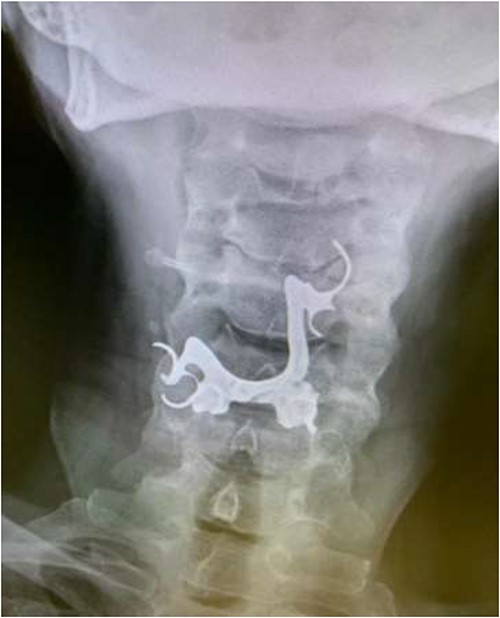

The final case is of a 75-year-old female who presented to hospital after inhalation of her dentures (Figs 6 and 7). After discussion with the anaesthetic team, apnoeic oxygenation was once again utilized in order to remove the foreign body without risk of dislodgement and to decrease the risk of a potential surgical airway (Fig. 8).

Lateral neck X-ray showing radio-opaque object in the upper airway.